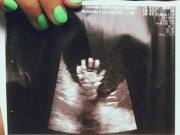

Cả gia đình sản phụ vỡ oà hạnh phúc.